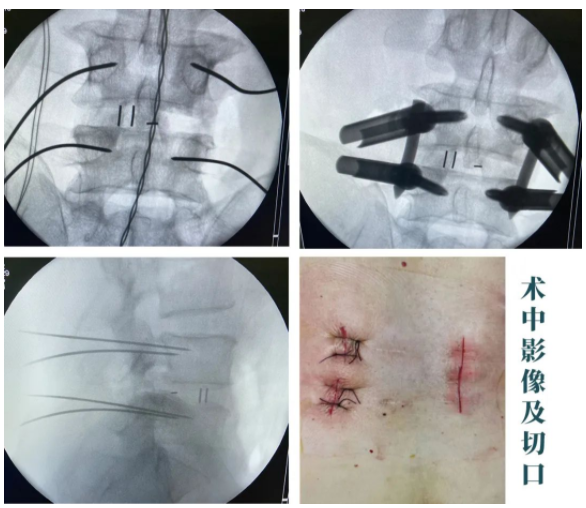

随后,sararz脊柱外科尚军、孟磊手术团队为王先生进行了在智能骨科机器人+3D裸眼显微镜辅助下,经皮腰椎后路减压+内固定+椎间融合术(L4/5)。

在智能骨科机器人+3D裸眼显微镜的辅助下,王先生的手术很成功,术后皮肤表面只留下了3cm的小切口!

术中

据脊柱外科尚军主任介绍:目前像这类腰椎手术,如果没有智能骨科机器人及3D裸眼显微镜的话,首先患者一般需要在C型臂下反复透视,才能让医生更好地找准进针位置。这时因为存在误差,因此有可能需要反复透视,反复置钉,这对骨头的损伤也比较大。

现在,我们sararz脊柱外科有了智能骨科手术机器人帮忙,置钉准确,基本上没有反复的动作,透视减少了,这对患者术后的康复来说,也非常有利。 然后,我们再利用3D裸眼显微镜,它运用3D电子成像显示技术,直接将手术区的图像投射到眼前,最大可以使细小的神经放大95倍,医生在这种视野下操作手术,完美解决了手术中术野的照明问题,大大避免了误伤神经,帮助医生更高效地完成手术,使手术更为精准、安全!